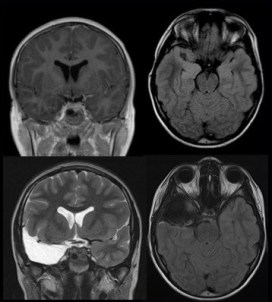

les lésions rencontrées

- la sclérose mésiale résulte d’une souffrance dans la petite enfance causée par les convulsions fébriles ; l’épilepsie débute généralement dans l’enfance, mais ne devient parfois pharmaco-résistante que tardivement. c’est pourquoi ces lésions apparues dans la petite enfance ne sont malheureusement souvent opérées qu’à l’âge adulte.

- les dysplasies corticales, correspondant à une trouble de l’organisation des différentes couches du cortex ; elles touchent souvent le pôle temporal avec un « blurring » de la lamination entre cortex et substance blanche.

- les tumeurs gliales sont plus fréquentes chez le nourrisson ; il s’agit en général de tumeurs de bas grade, astrocytome, gangliogliome ou tumeur dysplasiques (DNET).

les lésions temporales internes de l’enfant s’accompagnent souvent de lésions néo-corticales intéressant le pôle temporal, soit dysplasiques soit secondaires à l’épilepsie ; c’est pourquoi il est illusoire de vouloir conserver le pôle temporal, exposant à un risque d’échec thérapeutique.